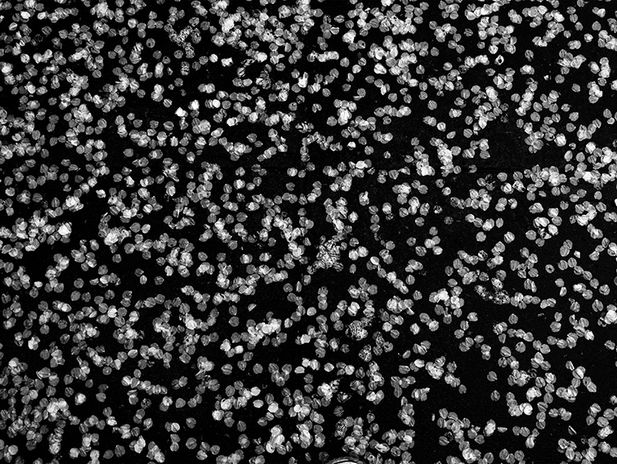

Sohoki je japonska beseda, ki je v uporabi od 16. stoletja kot splošni izraz za optično bolezen, ki povzroča vidno okvaro, dobesedno pomeni »senca na dnu«. Izraz aosohoki, dobesedno »zelena senca na dnu«, se je uporabljal za opis glavkoma. Obstaja teorija o izvoru te besede, in sicer ao (zelena) izvira iz Hipokratovega zapisa, kjer je navedeno, da se zenica obarva v zeleno barvo Sredozemskega morja preden dokončno oslepi. Čeprav se pojavi že precej nazaj v preteklosti in je eden najpogostejših vzrokov za okvare vida na Japonskem, vzrok za glavkom še ni popolnoma raziskan in zdravljenje ni vedno učinkovito.

Tak primer je tudi glavkom mojega očeta. Dnevne aplikacije zdravil že štirinajst let in operacija niso uravnali visokega pritiska v njegovem očesu, kar je povzročilo počasne, vendar napredujoče poškodbe vizualnega polja. Vsako dan se zbudi v rahlo bolj temno jutro in ko skuša nekaj prijeti, njegove roke pogosto zajamejo zrak namesto želenega predmeta. Oče je večino svojega življenja pisal dnevnike. Na potovanjih je fotografiral. Med uredniško kariero, ki je trajala skoraj petdeset let, je bil vedno obkrožen s knjigami in različnimi zapisi. Vendar zaradi glavkoma branje in pisanje zanj nimata več pomena. Prenehal je uporabljati stare dnevnike in začel uporabljati beležnico Visual Ease Black, pri čemer je uporabljal bela pisala na črnem papirju, kar olajša branje ljudem s poslabšanim vidom. Sčasoma pa je moral opustiti tudi to beležnico.

Čeprav je videti, da kljub napredovanju slepote mirno sprejema svojo usodo, pridejo trenutki, ko se obupano oklepa svojega pojemajočega vida, kot bi se boril, da bi ga ustavil pred popolnim izginotjem. Obenem okrog sebe gradi zid, da bi se zavaroval pred sočutjem ljudi, ki lahko vidijo tisto, česar sam ne more, in hkrati ne morejo videti tistega, kar on lahko. Ko kukam okrog tega zidu, opažam bežne podobe očetovega gibanja v in iz sence na dnu, nestabilno hojo, a hkrati čvrsto iskanje novih možnosti za dojemanje sveta okrog njega. Njegovo potovanje proti slepoti se premika naprej in nazaj med svetlobo in senco, podobno kot valovi, ki se premikajo k obali in stran od nje.